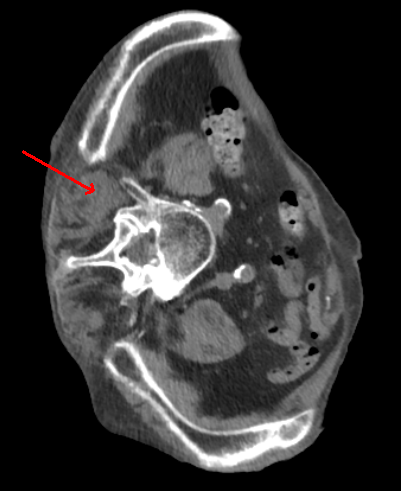

Case Presentation: An 87-year-old male presented to the emergency department following a syncopal episode, preceded by one week of generalized weakness, poor oral intake, and acute left leg pain. His medical history included heart failure with preserved ejection fraction (HFpEF), atrial fibrillation (AFib), chronic kidney disease (CKD) stage IV, rheumatoid arthritis (RA) managed with chronic steroids, and vertebral compression fractures.On presentation, he was hypotensive and in AFib with rapid ventricular response, which resolved with fluid resuscitation. Given concern for a pulmonary embolism, a CT angiogram was performed. While negative for embolism, imaging incidentally revealed new bilateral pulmonary nodules and multiple mass-like areas of enhancement scattered within the muscles of the lumbar spine and pelvis, raising suspicion for metastatic malignancy.An ultrasound of the left leg identified a new soft tissue mass, which, along with a left paraspinal mass, was biopsied. Pathology confirmed Nocardia cyriacigeorgica. The Infectious Disease team initiated treatment with linezolid and imipenem. Brain imaging subsequently revealed CNS dissemination. The patient’s hospital course was further complicated by serotonin syndrome, severe malnutrition, and profound deconditioning, limiting his ability to recover. Despite aggressive medical management, his overall condition continued to decline. Palliative medicine was consulted, and the patient was ultimately transitioned to comfort-focused care.